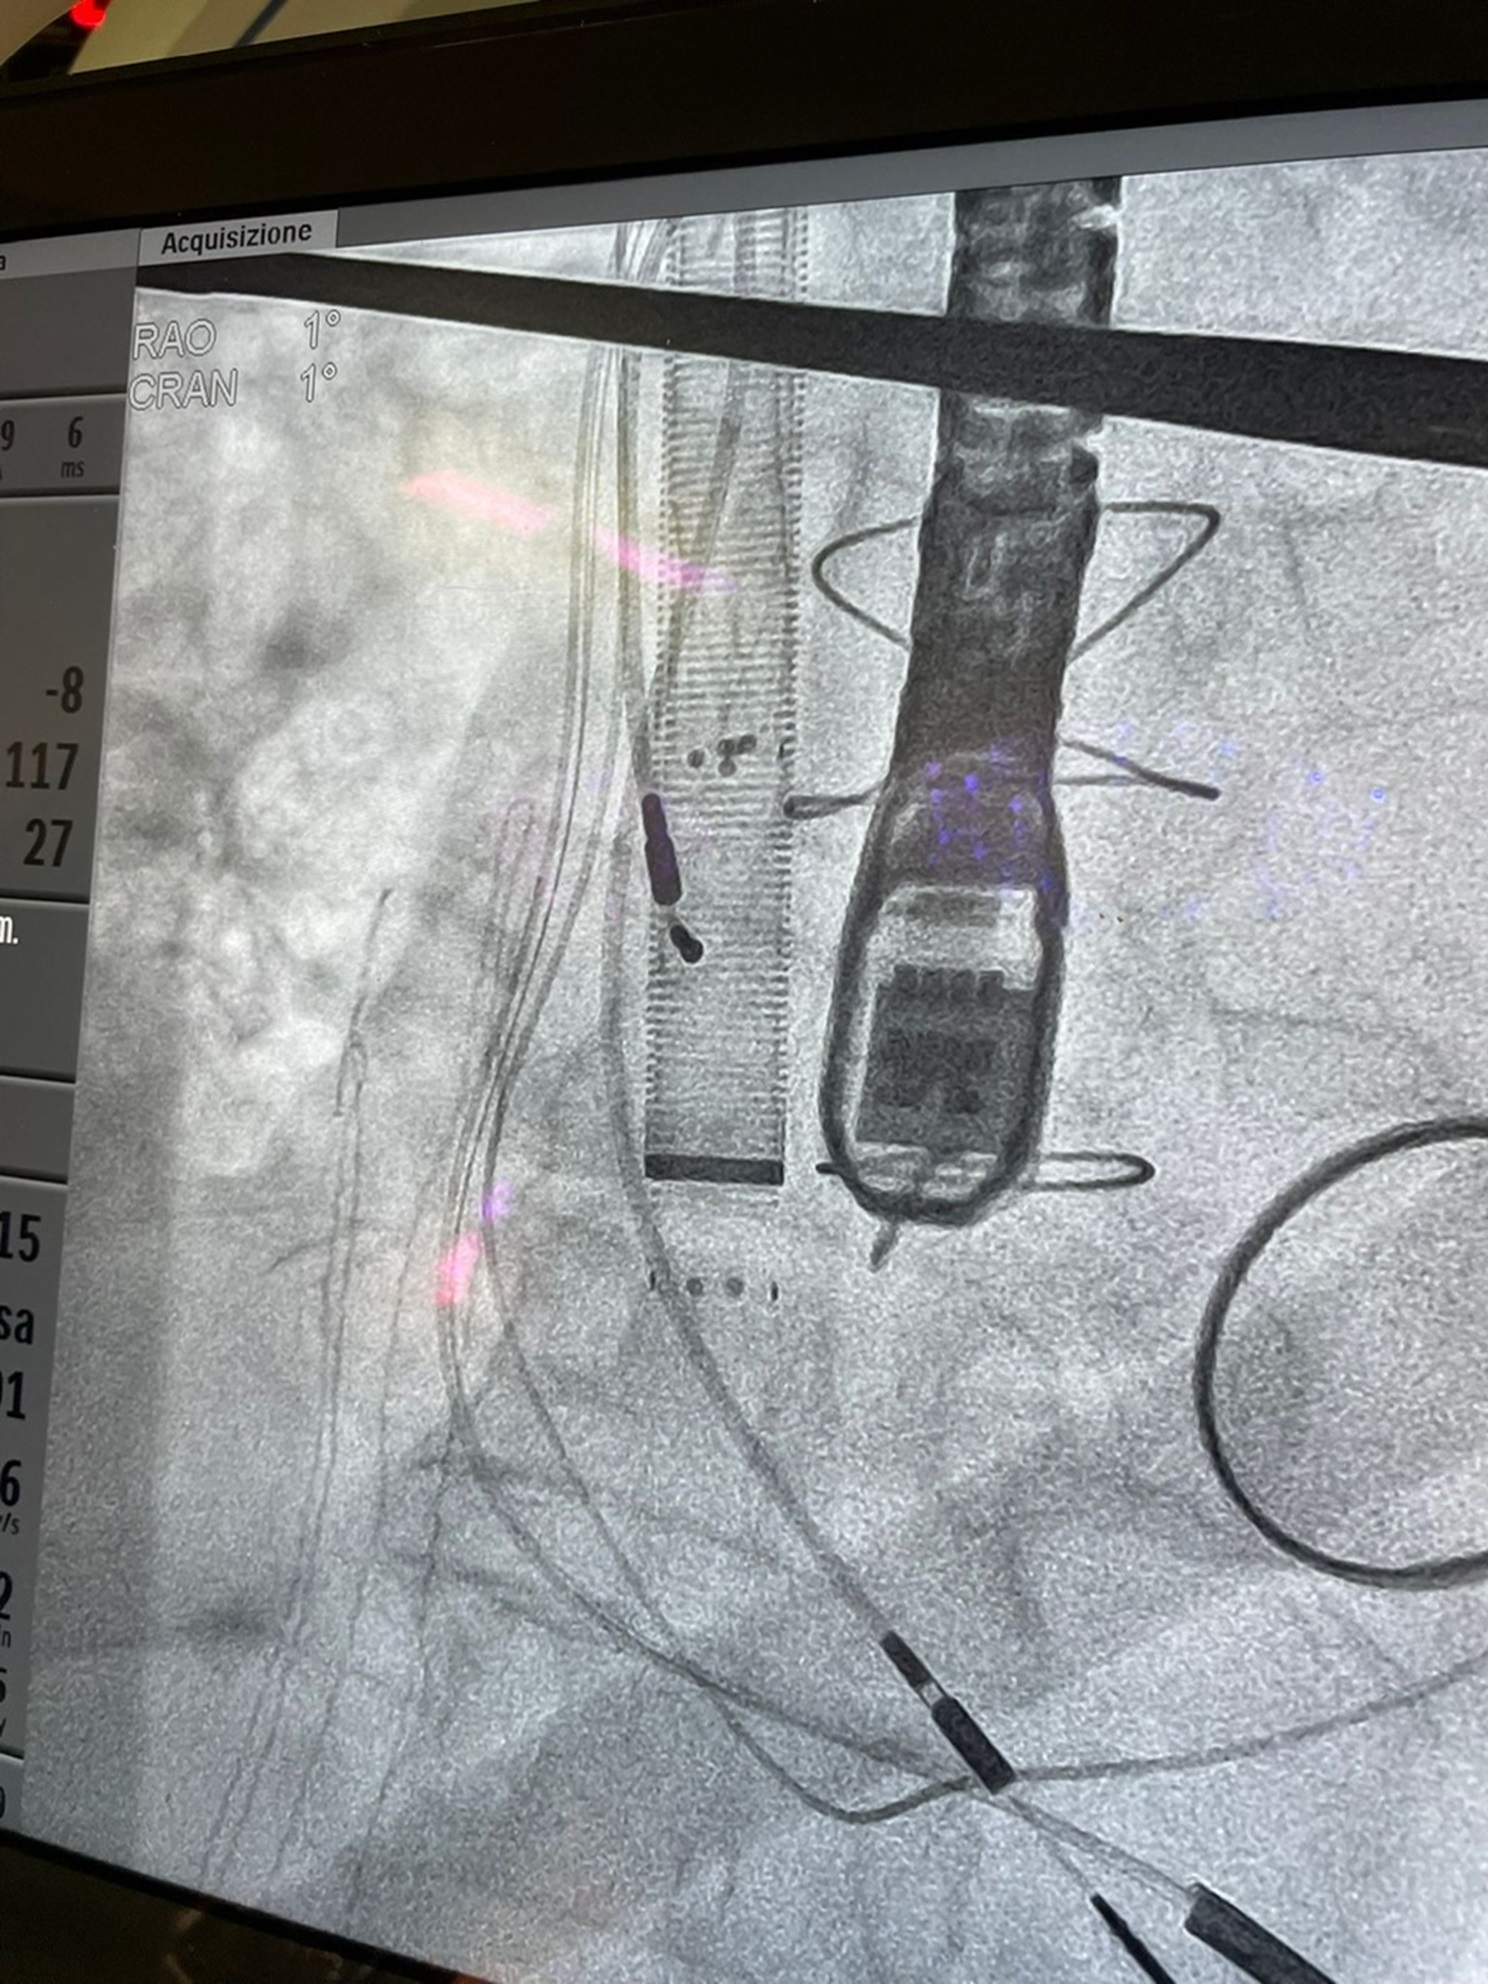

CARDIOCHIRURGIA SISTEMA ANGIOVAC

Il nuovo sistema di drenaggio venoso Angiovac è stato utilizzato per la prima volta con successo nell’Unità Operativa Complessa di Cardiochirurgia dell’AOU del Policlinico “Rodolico – San Marco” di Catania diretta da Salvatore Lentini.

Un delicato intervento con l’utilizzo della procedura al suo debutto, in particolare, è stato eseguito in una delle moderne sale operatorie del presidio “Rodolico” di via Santa Sofia, per l’asportazione di una grossa “vegetazione fungina endocardiaca dalla valvola tricuspide”, vale a dire una serie di trombi formatisi nell’atrio destro del cuore di una donna settantenne, a seguito dell’infezione di cavi legati al pace maker per l’elettrostimolazione cardiaca.

La metodica AngioVac, estremamente mininvasiva, in questo caso ha incluso una cannula di aspirazione, inserita da una vena giugulare, dotata alla sua estremità di una struttura espandibile a forma di ventaglio così da poter catturare e aspirare agilmente la massa fungina.